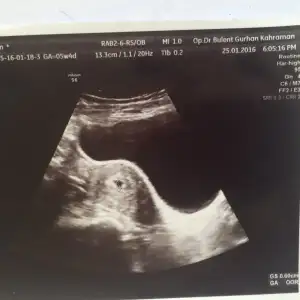

Buda ablasının özlemle bekleyip sonunda kavuştuğu kardeşi :KK37:

• 1453987768160-210884203.webp

1453987768160-210884203.webp

12,2 KB · Görüntüleme: 119